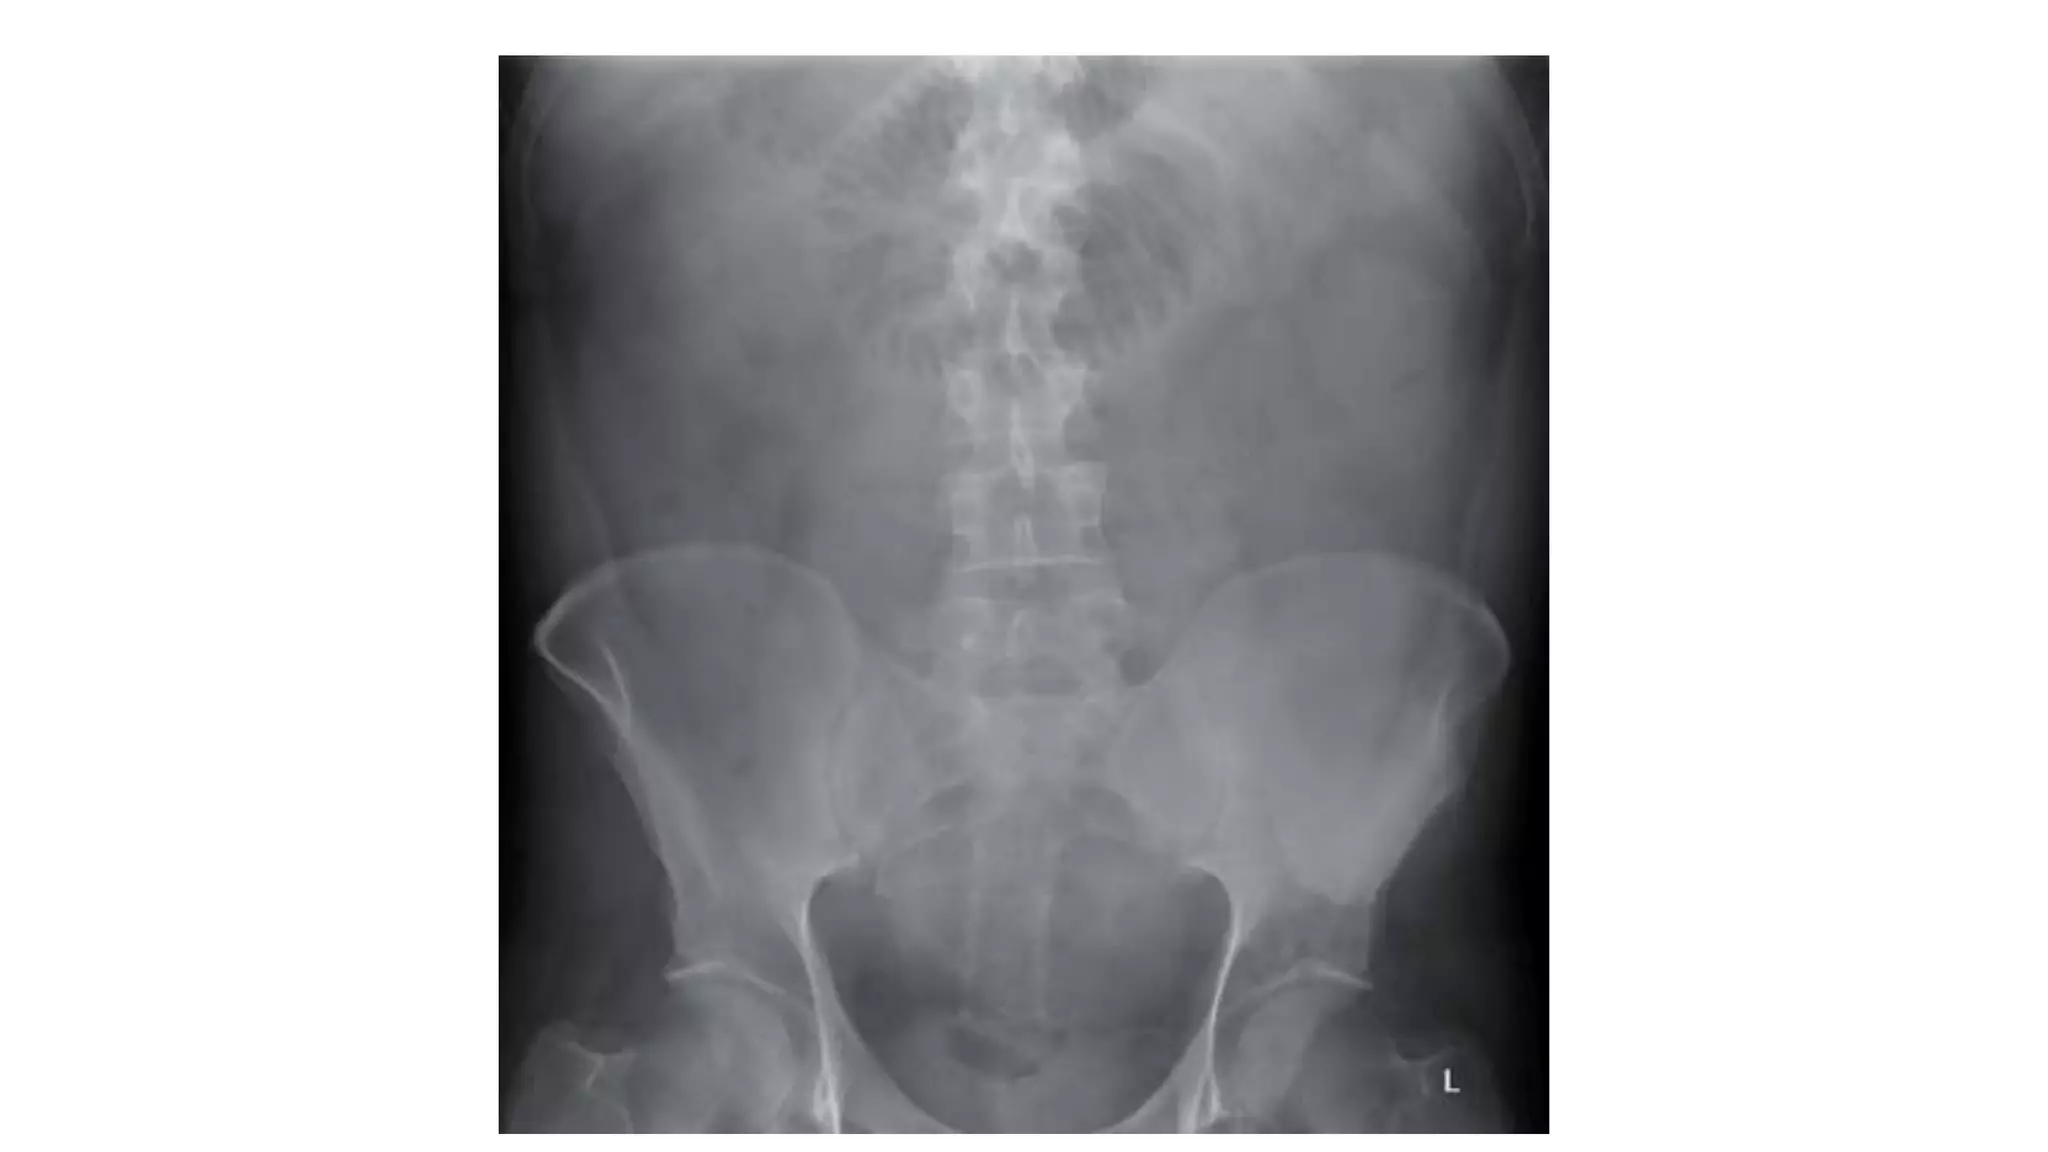

Who wants tobe a hero ?

• 62.

Pick up 3findings